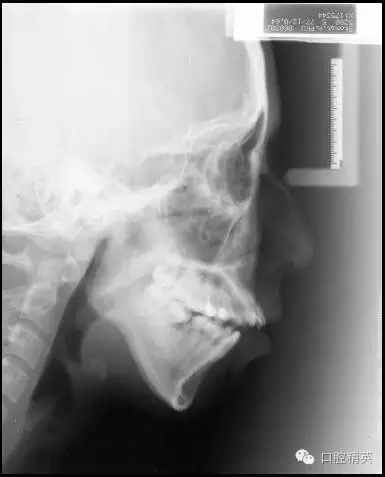

既然我們很難改變患者髁突生長(zhǎng)不足的問題,就只好從控制其上頜骨及磨牙區(qū)的垂直生長(zhǎng)著手了,由于抑制生長(zhǎng)本非易事,控制患者的磨牙高度就成了控制其下頜平面最切實(shí)可行的手段。而通過壓低磨牙來控制高角患者的下頜平面,乃至實(shí)現(xiàn)其下頜平面的前上旋轉(zhuǎn)正是后部垂直向控制的概念及意義所在(圖1)。

圖1 通過壓低磨牙進(jìn)行后部垂直向控制